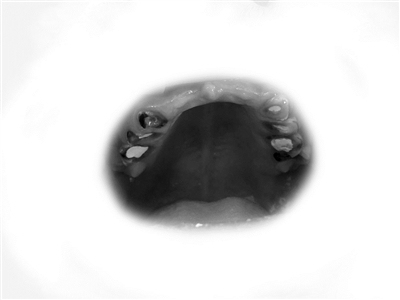

28颗牙齿拔掉8颗、折断10颗

其余的也没有一颗完整的

男孩被妈妈带到章主任这里的时候,满口牙齿已经惨不忍睹。成年人的口腔里,有功能的应该有28颗牙齿,上下12颗门牙+8颗前磨牙+8颗磨牙。男孩的这28颗牙齿,其中上门牙6颗、下磨牙2颗,因为烂得太彻底,已不得不拔掉了。还有10颗牙齿因为被饮料腐蚀得脆弱不堪而折断,甚至齐根折断与牙龈齐平了。满口牙齿中,还算“有点样子”的只剩6颗下门牙,但也被腐蚀得很单薄,牙体几乎变透明了,基本上只要一咬骨头,也会马上碎裂。

因为从小烂牙齿,不能咬硬东西,什么骨头呀豆子呀都不能吃,这也影响到了面部骨骼发育,男孩的上颌骨骨量不足,显得窄小,闭着嘴的时候,是“地包天”。他平时不敢笑,要笑的时候,也只好抿着嘴,怕被同学笑话。